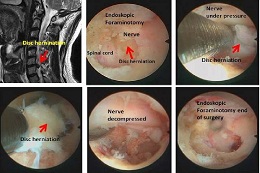

Pain management (also called pain medicine or algiatry) is a branch of medicine employing an interdisciplinary approach